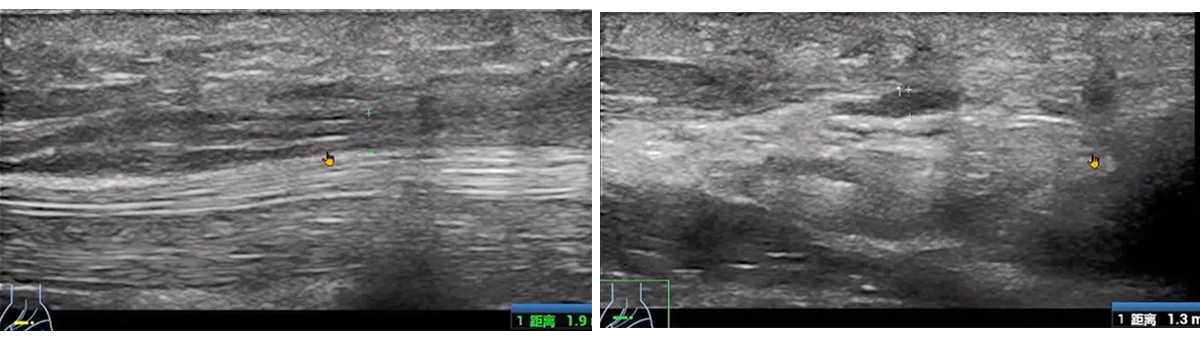

A traumatic injury to the forearm caused by a dropped drill led to impaired extension of the thumb and index finger.

The handheld ultrasound machine showed significant swelling and thickening of the deep branch of the radial nerve, with disrupted and non-continuous nerve structures.

Here, the portability and precision of the ultrasound machine were essential for assessing the extent of nerve damage and guiding further management.